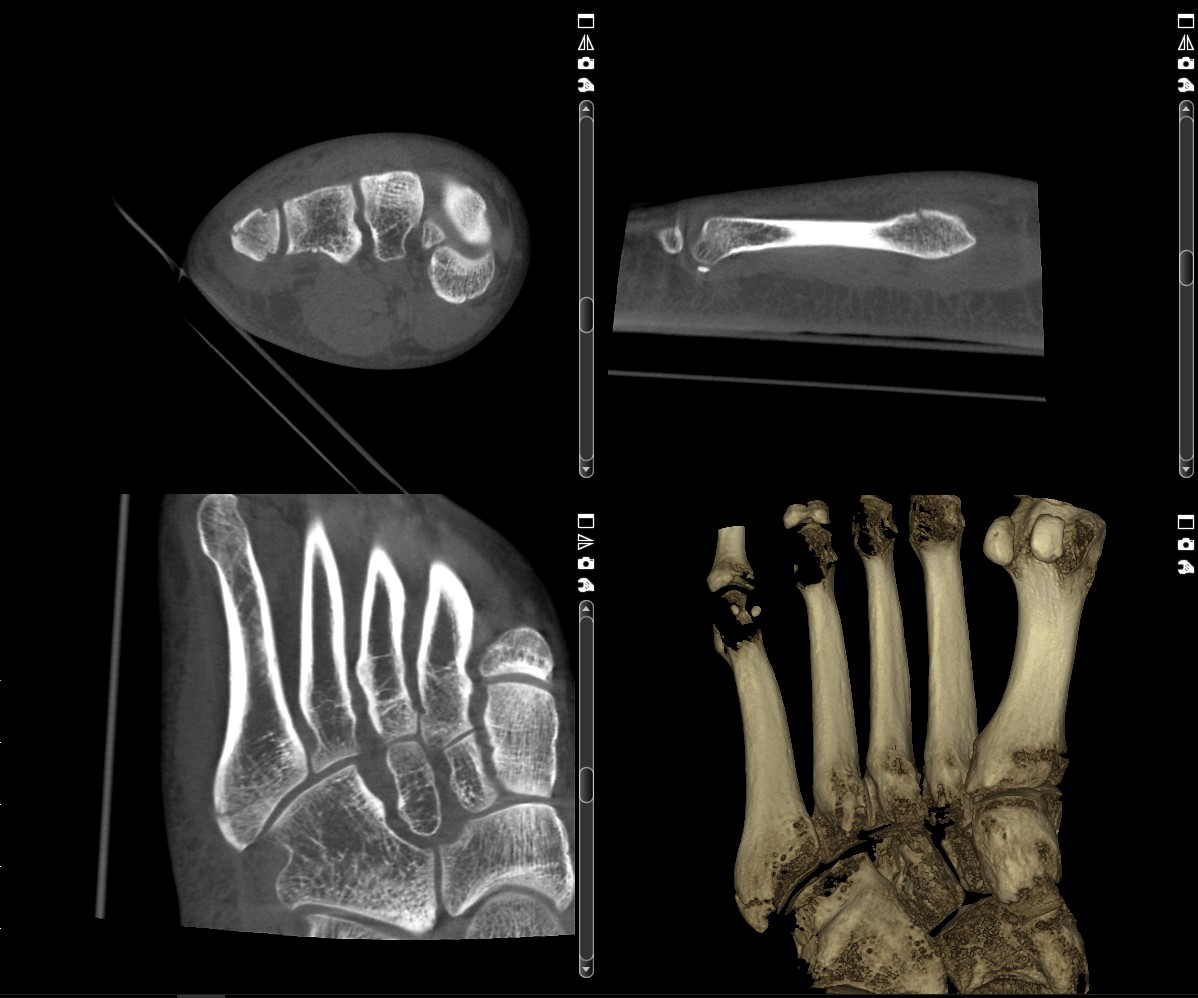

DVT Fuß:

23 Jahre alter Patient mit einem basisnahen Bruch am fünften Mittelfußknochen. Die 3-D Darstellung zeigt eine durchgängige Frakturlinie. In der konventionellen Röntgenaufnahme konnte der Bruch nicht ausreichend dargestellt werden.